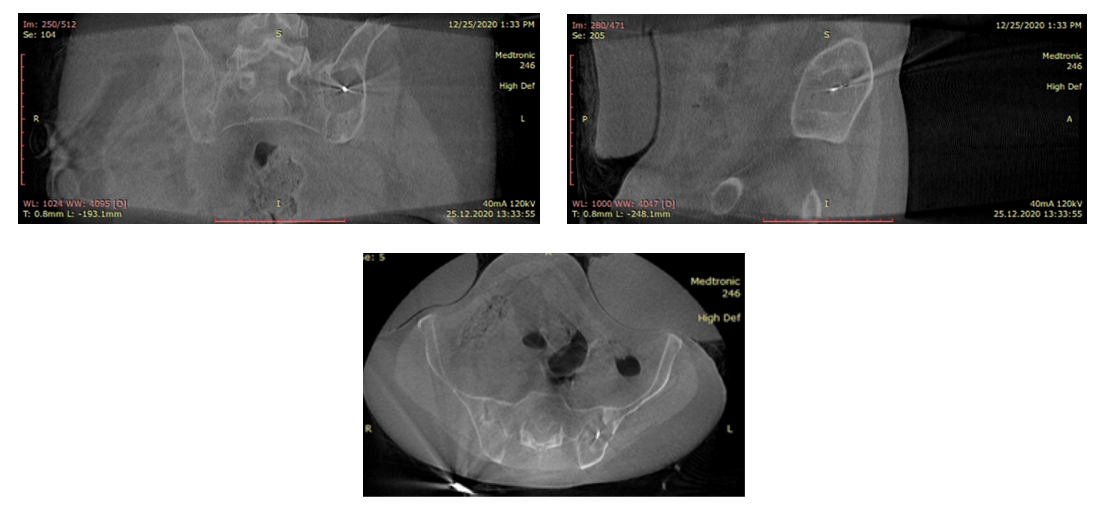

- Tomografi görüntüsünde belirgin kemik yıkımı.

- Ameliyathanede O-arm cihazı rehberliğinde, cihazın (prob) tümörün merkezine yerleştirilmesi.

- Her üç kesitte cihazın tümörün tam merkezinde olduğu teyit edildi.